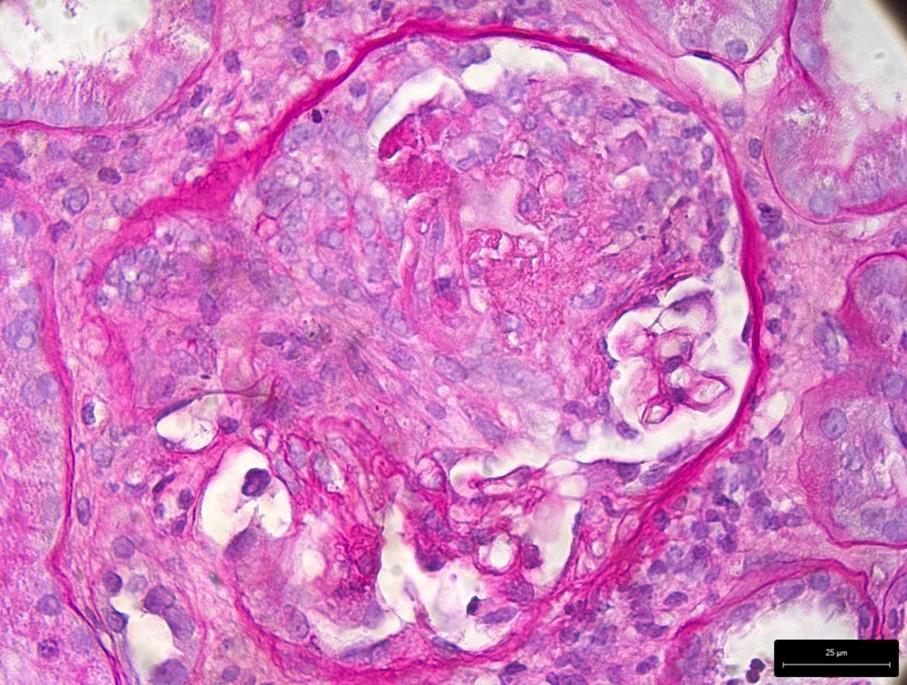

La biopsia renale consentiva la diagnosi di AAV, evidenziando una glomerulonefrite proliferativa extracapillare necrotizzante (Figura 1), una glomerulosclerosi segmentaria e globale focali (Figura 2), un diffuso danno tubulare acuto (Figura 3) e un focale fibroedema ed infiltrato interstiziale. L’immunofluorescenza mostrava sfumati depositi e aspecifici di IgM (+), due glomeruli contenenti semilune risultavano positivi per fibrinogeno (2–3+), in un glomerulo era presente necrosi fibrinoide. Non si rilevavano depositi di IgG, IgA,

Figura 1. Glomerulonefrite proliferativa extracapillare necrotizzante.